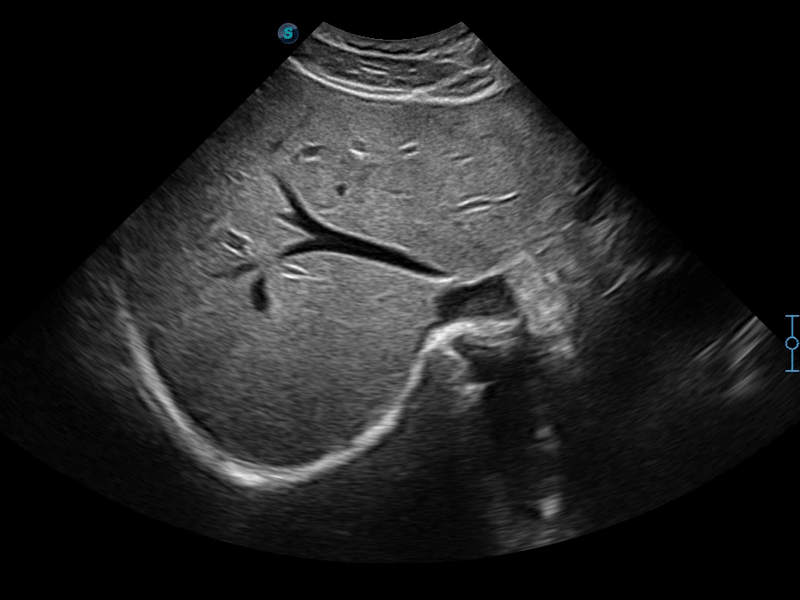

凭借狗万官方网站先进的成像技术和优异的探头技术提供的清晰的图像表现,您可以更自信地做出临床决策。

单晶体凸阵探头